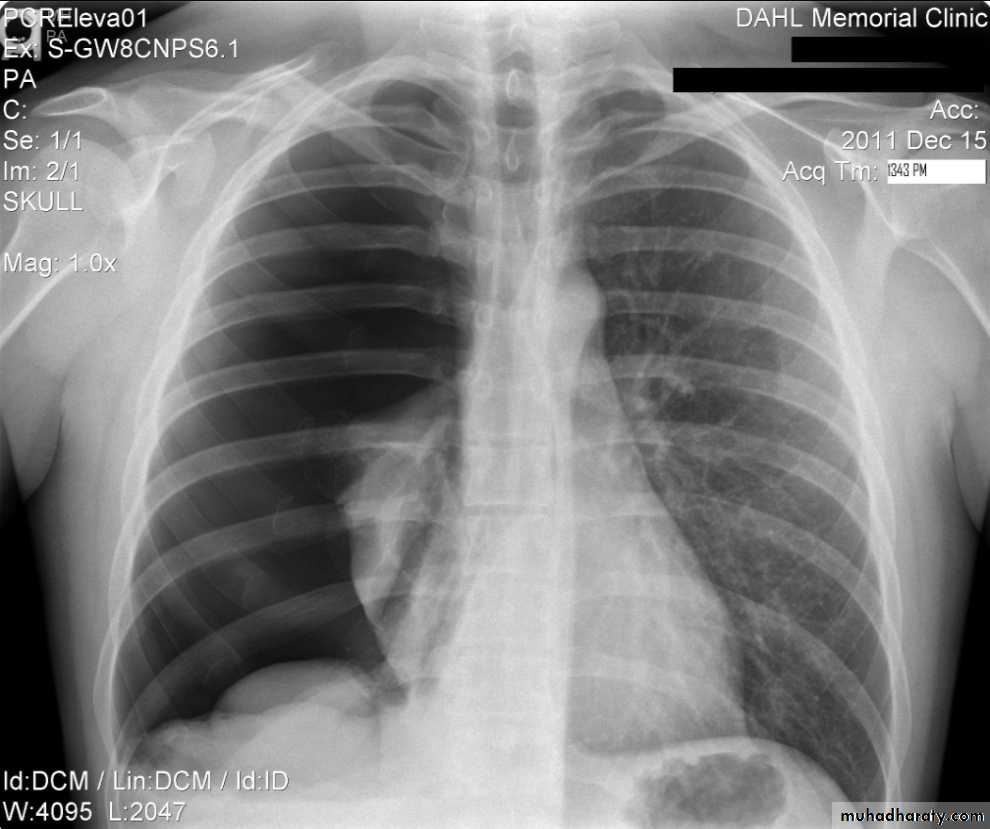

Pleural effusionPleural effusion tends to be used as a catch-all term denoting a collection of fluid within the pleural space. This can be further divided into exudates and transudates depending on the biochemical analysis of aspirated pleural fluid. Essentially it represents any pathological process which overwhelms the pleura's ability to reabsorb fluid.

Radiographic appearances

Plain radiographChest radiographs are the most commonly used examination to assess for presence of a pleural effusion, however it should be noted that on a routine erect chest x-ray as much as 250-600 ml of fluid is required before it becomes evident 6. A lateral decubitus film is most sensitive, able to identify even a small amount of fluid. At the other extreme, supine films can mask large quantities of fluid.

Both PA and AP erect films are insensitive to small amounts of fluid. Features include:

blunting of the costophrenic angle

blunting of the cardiophrenic angle

fluid within the horizontal or oblique fissures

eventually a meniscus will be seen, on frontal films seen laterally and gently sloping medially (note:

with large volume effusions, mediastinal shift occurs away from the effusion (note: if coexistent collapse dominates then mediastinal shift may occur towards the effusion)